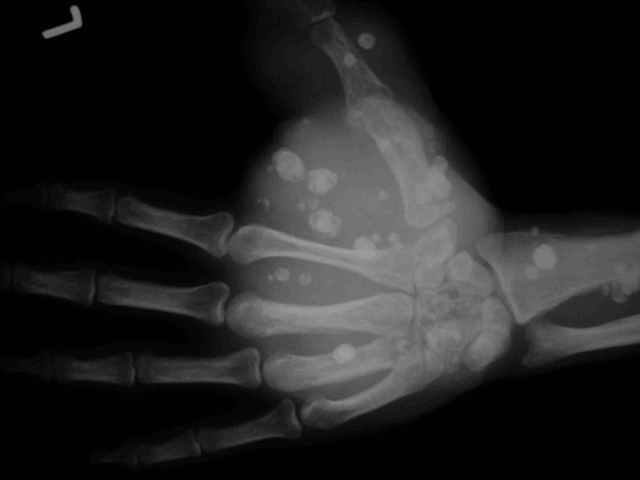

Гемангиома кисти

Нужен совет. Мужчина средних лет, деформация кисти с детских лет, а в поликлинику обратился за инвалидностью. Кисть вполне функциональна и безболезненна, боли появляются только при сильном напряжении кисти.Жду ответа, с наилучшими пожеланиями,Евгений Чекашкин

Я показал случай нашим микрохирургам. Они

рекомендуют биопсию для уточнения диагноза (нодуллярный синовит? синовиальная опухоль?). Оперативное лечение вероятнее всего многоэтапное, возможна резекция первого луча с последующие пластикой.

У меня нет опыта радикальной хирургии таких обширных геменгиом кисти, приходилось оперировать на запястье и не такие массивные. В тех ситуациях

после мобилизации опухоли я перевязывал питающие сосудистые пучки и убирал опухоль - осложнений в функциональном плане не возникало. Насколько я себе представляю, по сути своей хирургия в данном случае основана на том же принципе. Проблема только в том, что для того , чтобы выделить эту опухоль в зоне большого пальца и тенара потребуется обширная диссекция( межмышечная и подкожная локализация опухоли), которая в результате (не обязательно, но вероятность присутствует) приведет формированию рубцовых ткане с последущим нарушением функции кисти, возможному некрозу кожного лоскута. Видимо, это и останавливало коллег, консультирующих этого больного до меня, от радикального вмешательства. С другой стороны, рост опухоли у больного начался в детстве и то, что он обратился в госпиталь только в зрелом возрасте свопросом об инвалидности( не о лечении) дает представление о личностной характеристике больного, совершенно немотивирован, предел желания - пенсия по инвалидности. В такой ситуации, надеюсь согласитесь со мной, вряд ли можно рассчитывать на хороший функциональный результат после хирургии. Есть ли у вас наблюдения в практике лечения гемангиом склерозирующими препаратами, используемыми пр и венозном варикозе нижних конечностей. Если да, то было бы интересно узнать какие результаты.